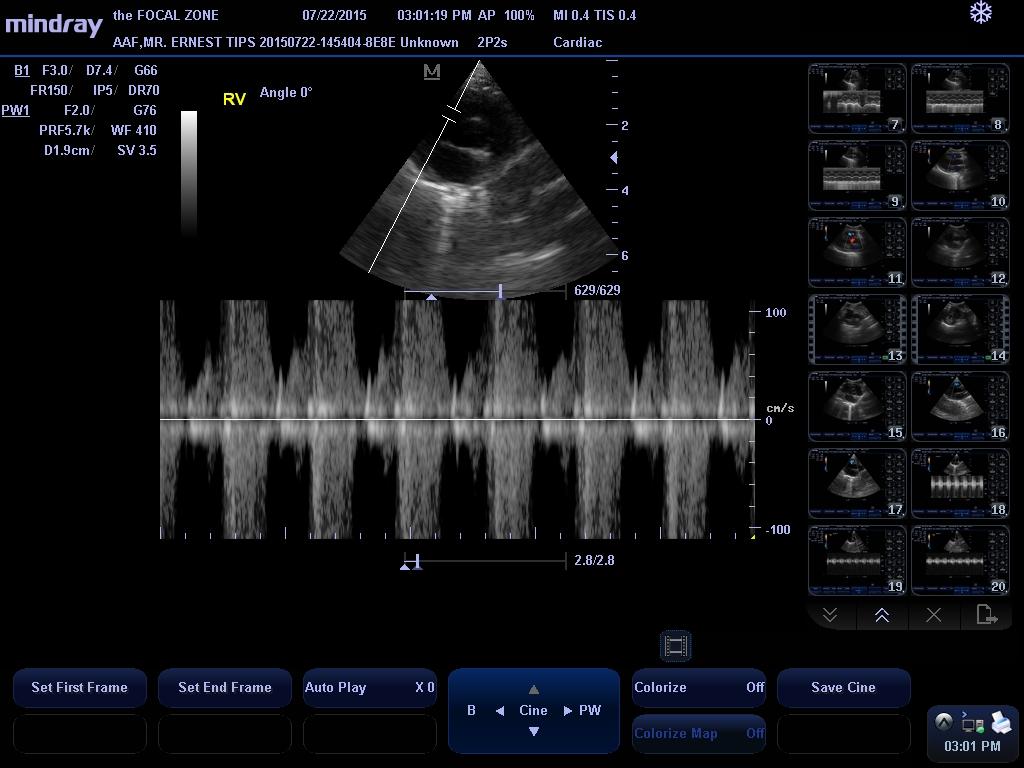

LVOT Vmax – 0.80 m/s

RVOT Vmax – 0.70 m/s